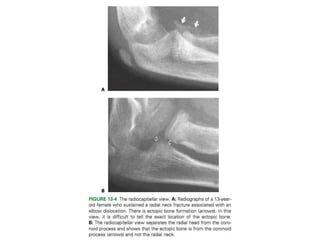

A: Acute injury films revealing small

displacement of radial head fracture on the

flexed elbow anteroposterior (AP) view and

subtle posterior subluxation not originally

appreciated on the lateral view.

B: Follow-up radiographs at 1 week noted more

difficulty interpreting the AP view in cast, and

more radiocapitellar posterior displacement on

the lateral view.